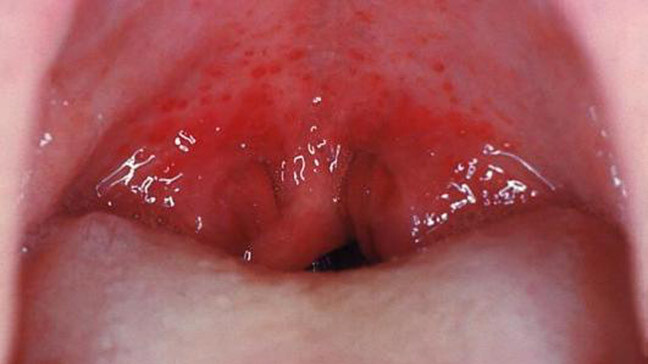

How To Use A Salt Water Gargle For A Sore Throat

Sore throats can be very unpleasant. Your throat may feel scratchy or dry, and it may even hurt to swallow. The Centers for Disease Control and Prevention (CDC) reports that viral infections — such as colds or the flu — are common culprits of sore throats. Other causes include strep throat, allergies and smoking. Within a week, most sore throats will get better on their own, but home remedies, such as a salt water gargle for a sore throat, can help you feel better in the meantime.

Why Does Gargling Salt Water Help?

Gargling with warm salt water is a widely recommended home remedy, but before you try it, you may be wondering how it works. The Mayo Clinic notes that warm liquids can help to ease the discomfort associated with a sore throat. Penn Medicine explains that salt water can help to kill bacteria, ease pain and loosen mucus, making it especially helpful in relieving your symptoms.

Home remedies aren't always enough to heal a sore throat, however. The CDC recommends seeing a doctor if you have symptoms of strep throat, such as a fever, pain when swallowing or red, swollen tonsils. You should also see a doctor if you have bloody saliva, difficulty swallowing or breathing, joint pain or any other symptoms that concern you.